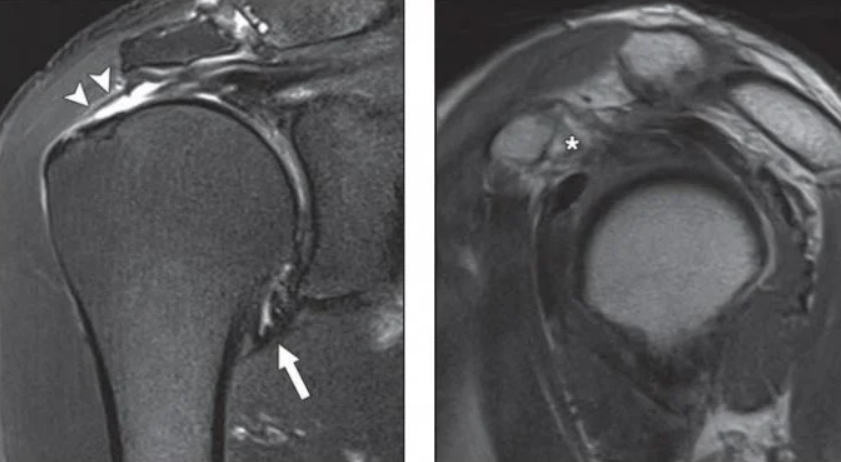

초음파상 저에코의 검은 음영으로 보이는 파열

MRI상 고신호로 관찰되는 완전파열로 인한 결손